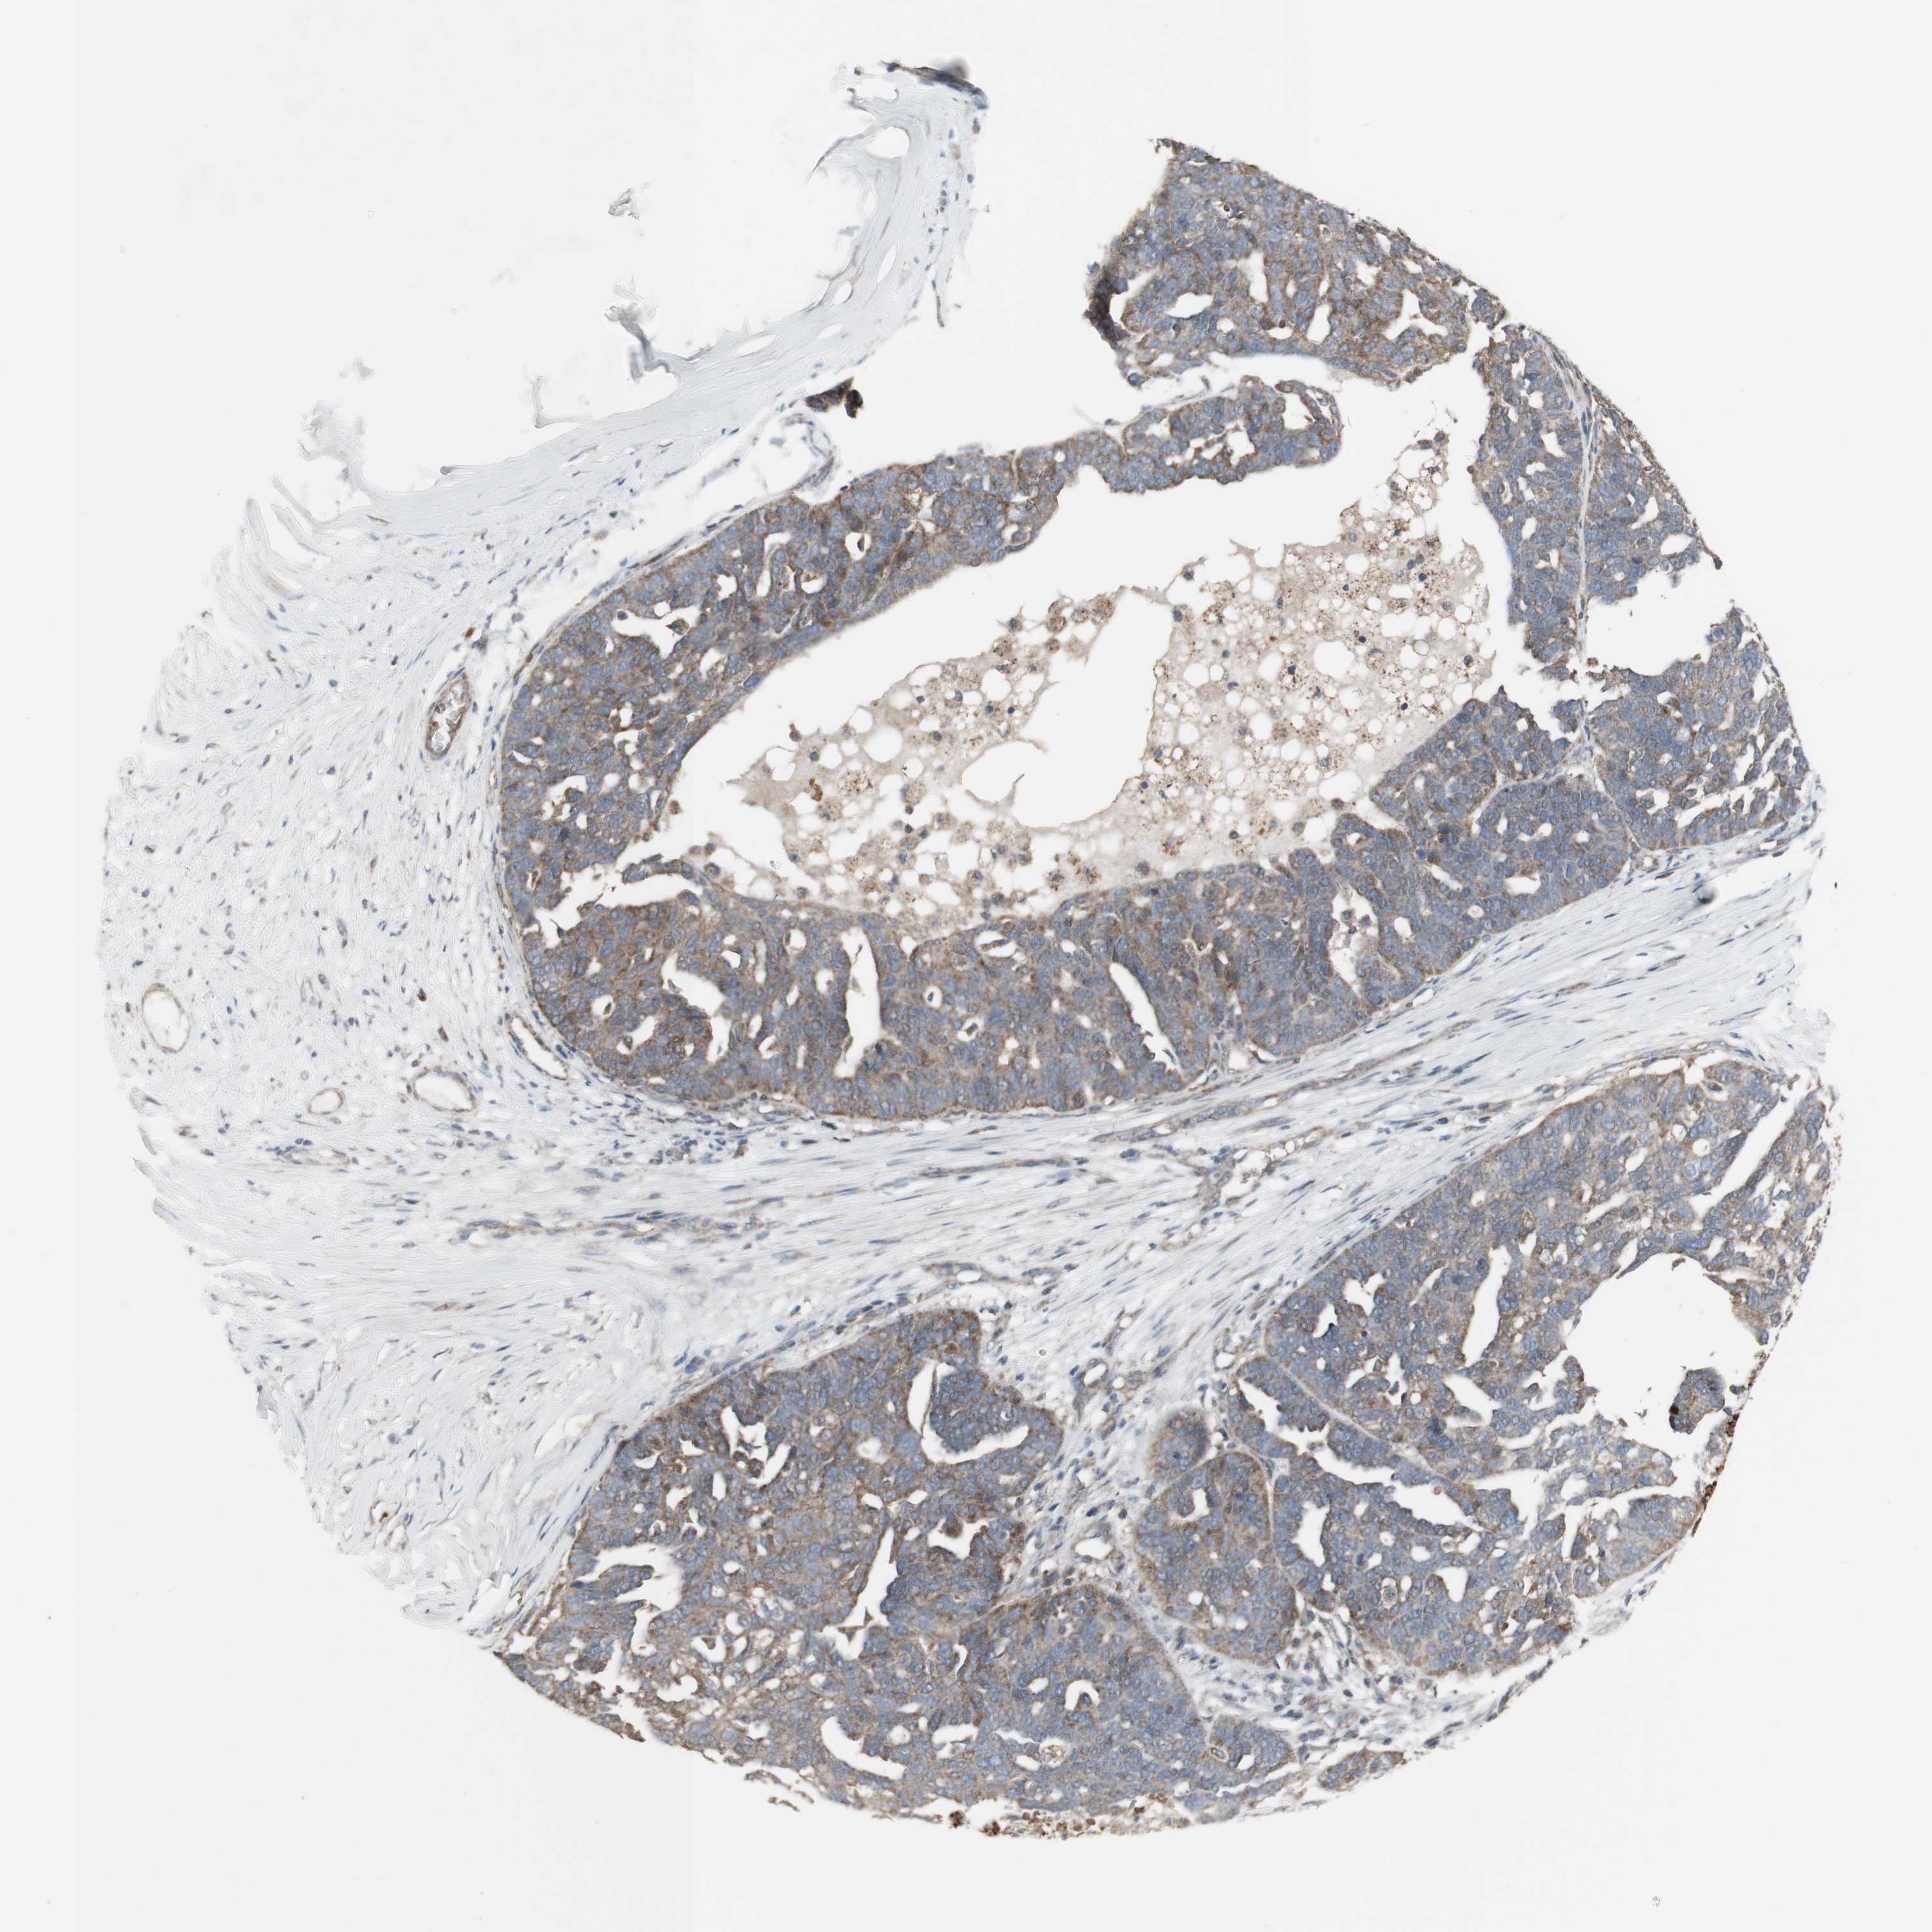

OVARIAN CANCER - Protein expressioni

A mouse-over function shows sample information and annotation data. Click on an image to view it in a full screen mode. Samples can be filtered based on level of antibody staining by selecting one or several of the following categories: high, medium, low and not detected. The assay and annotation is described here.

Note that samples used for immunohistochemistry by the Human Protein Atlas do not correspond to samples in the TCGA dataset.

Antibody stainingi

Antibody staining in the annotated cell types in the current human tissue is reported as not detected, low, medium, or high, based on conventional immunohistochemistry profiling in selected tissues. This score is based on the combination of the staining intensity and fraction of stained cells.

Each image is clickable and will lead to virtual microscopy that enables deeper exploration of all samples and also displays staining intensity scores, fraction scores and subcellular localization as well as patient and tissue information for each sample.

Antibody CAB016305

Carcinoma, endometroid